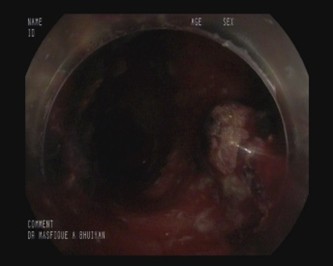

Colonoscopy image datasets are inherently heterogeneous, containing frames acquired under a variety of clinical conditions. As illustrated in Table 4, the data frequently exhibit artifacts that complicate polyp detection and segmentation. Examples include stool residues adhering to the intestinal wall, blood obscuring mucosal surfaces, or inflammation that alters tissue appearance. Additional challenges arise from image acquisition itself, such as low brightness, chromatic aberration, motion blur, or the presence of surgical tools in the field of view.

Table 4: Challenging Polyp image examples of BPD dataset.

Sl. no Image description Image Mask

1 Image containing polyp without any noise or challenging aspects [Uncaptioned image] [Uncaptioned image]

2 Image contains polyp with some stool dotting the intestinal wall [Uncaptioned image] [Uncaptioned image]

3 Image contains polyp with blood being present on the intestine wall [Uncaptioned image] [Uncaptioned image]

4 Image contains polyp in an inflamed intestine [Uncaptioned image] [Uncaptioned image]

5 Blurred or unfocused image containing polyp [Uncaptioned image] [Uncaptioned image]

6 Chromatic aberration distortion present in polyp image [Uncaptioned image] [Uncaptioned image]

7 Low brightness image containing polyp [Uncaptioned image] [Uncaptioned image]

8 Image with improper bowel preparation [Uncaptioned image] [Uncaptioned image]

9 Surgical tool present alongside polyp [Uncaptioned image] [Uncaptioned image]

10 Motion blur present in image [Uncaptioned image] [Uncaptioned image]